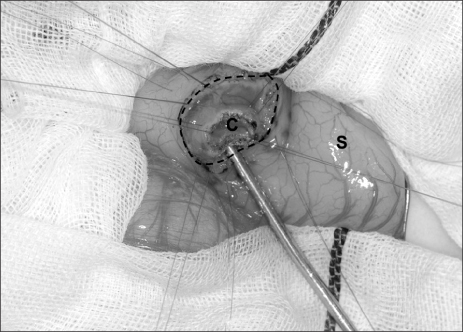

Fig. 2). Intraoperative cholangiography documented no communication between the cystic lesion and the bile or pancreatic ducts. Gastrotomy was performed transversally over the antrum just proximal to the cyst, and the cyst was delivered in toto through the incision. The cyst was incised (

Fig. 3) and a mucosectomy performed on the inner cyst wall. The upper part of the cyst wall was excised. The mucosa, submucosa and muscle of the margin of the cyst were approximated with interrupted absorbable sutures. Histopathologic examination was consistent with a gastric duplication cyst containing gastric mucosa (

Fig. 3Intraoperative findings of the duplication cyst. A transverse gastrotomy was performed to approach the cyst from inside the stomach. The cyst was incised and a mucosectomy was performed via a gastrotomy. C, cyst; S, stomach; broken line, transverse gastrotomy.